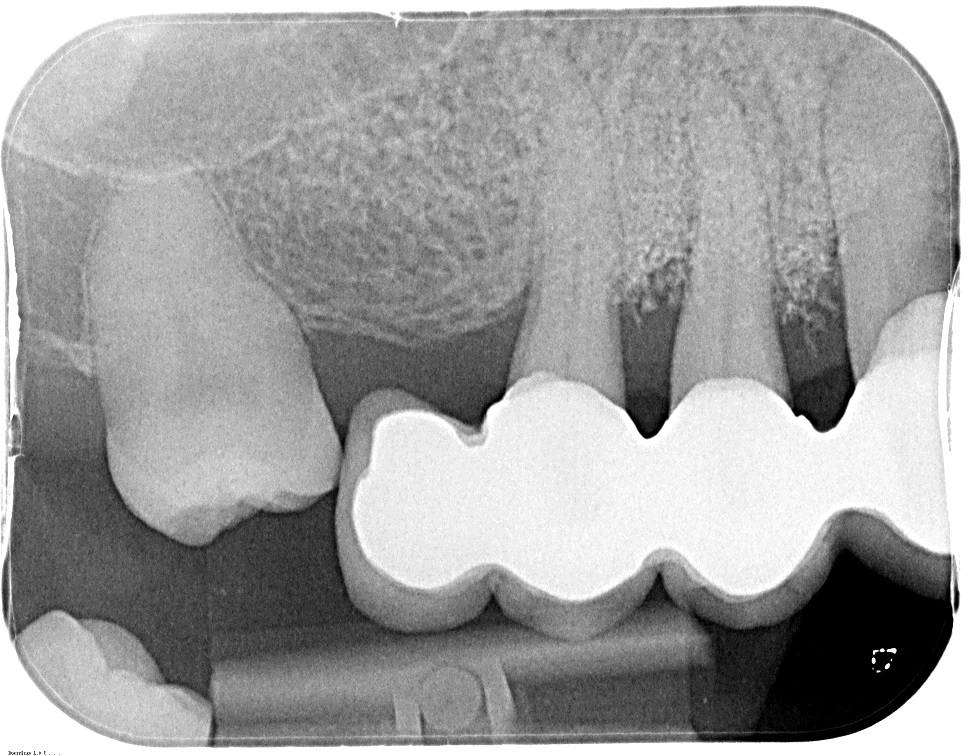

01/10 - Pre-operative OPG shows deep vertical intrabony defects on the distal aspects of teeth 13 and 14.GTR for the treatment of a deep three-dimensional intrabony defect using cerabone®, collprotect® membrane and Straumann® Emdogain® - Dr. T. Schwaar